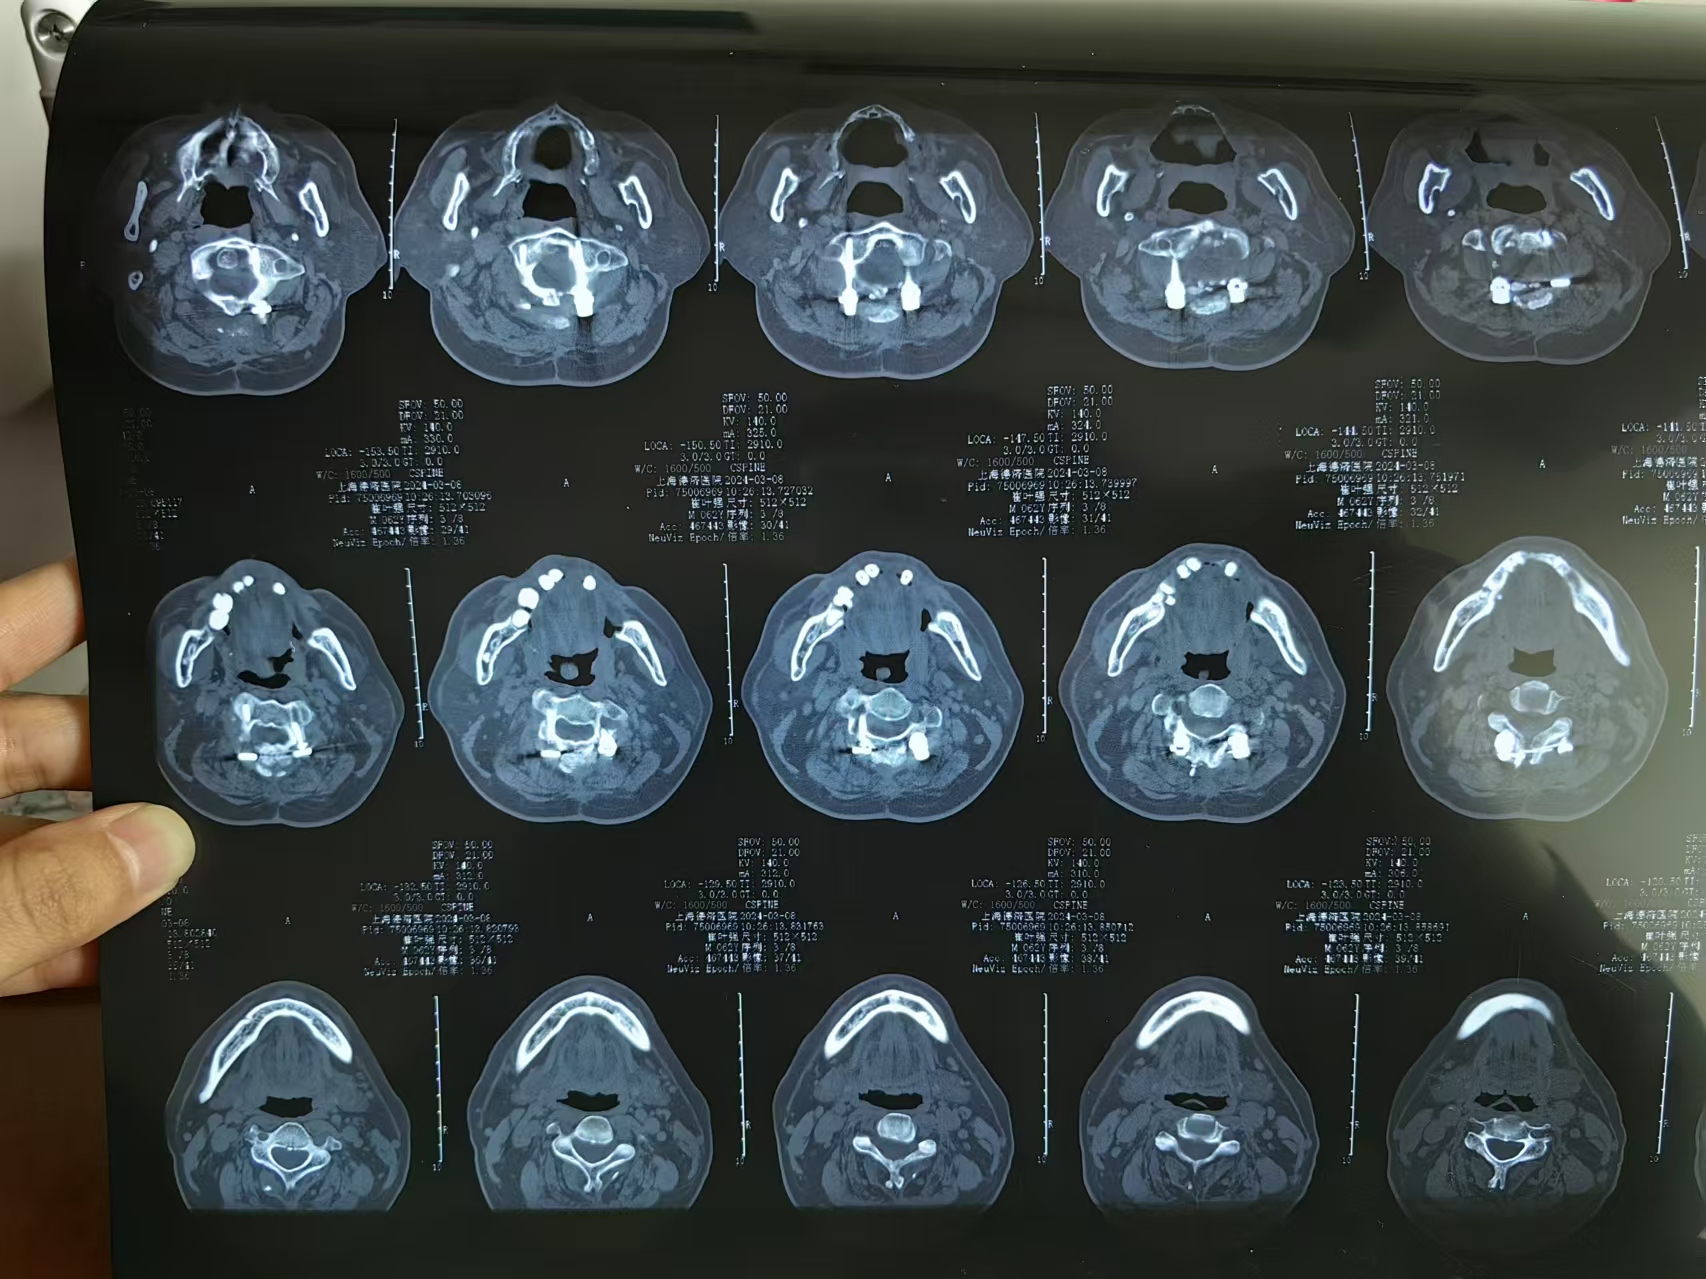

• 诊断:寰枢椎脱位,颅底凹陷

• 影像:

• 术后影像: